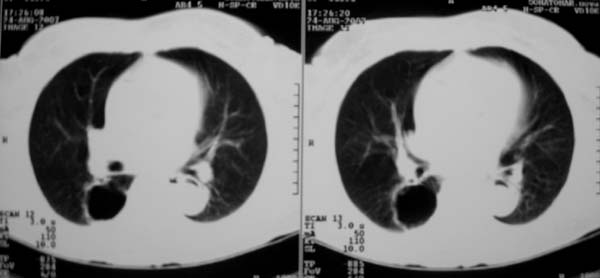

以下是引用zjzjr在2007-8-30 22:22:00的发言:[br]右上肺肺囊肿合并感染.右下肺肺大泡.左肺舌段感染.